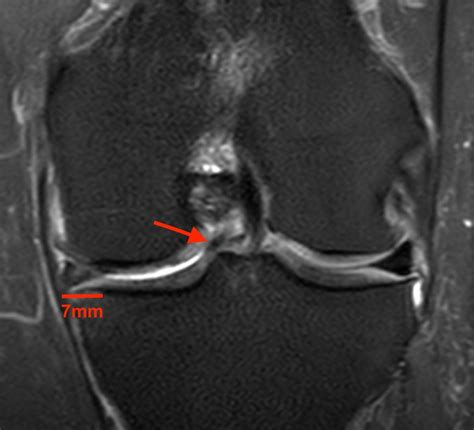

• Magnetic Resonance Imaging (MRI) to provide detailed images of the meniscus and surrounding structures. MRI is particularly useful in identifying the location and extent of the tear.

In some cases, an arthroscopy may be performed to directly visualize the meniscus and confirm the diagnosis. This minimally invasive procedure involves inserting a small camera into the knee joint through a tiny incision.